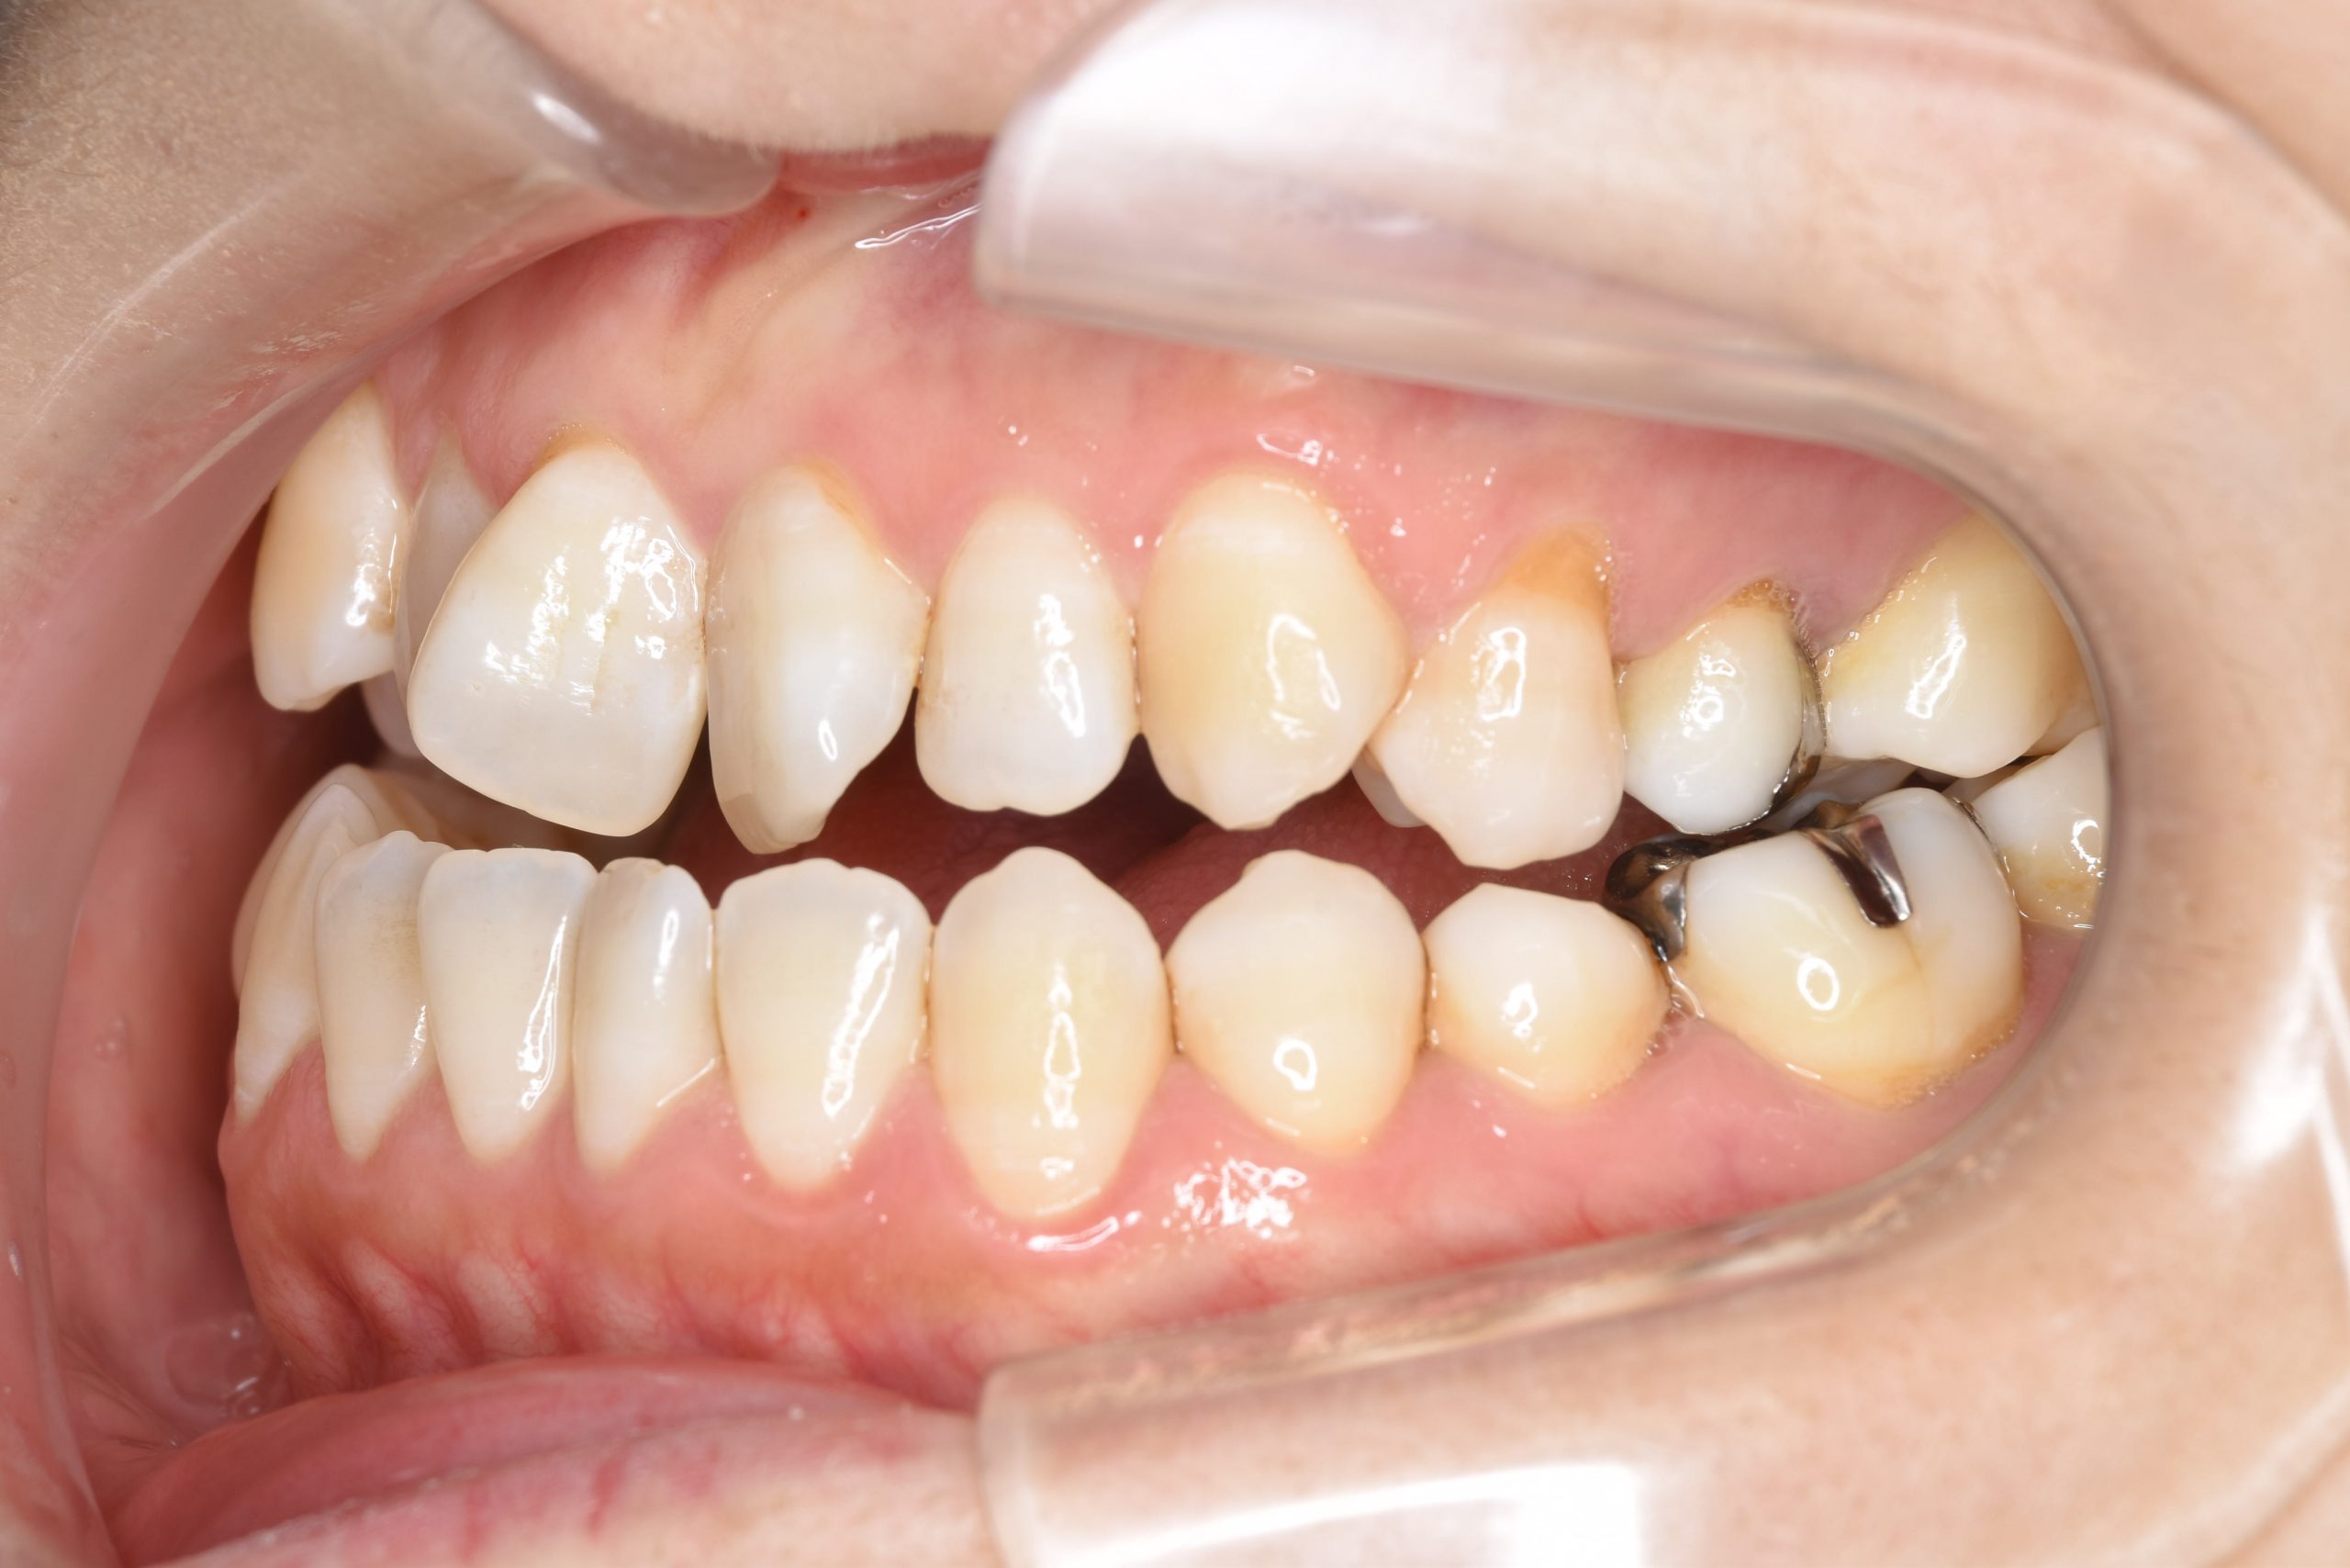

ビフォー

保険での矯正治療|症例_138

主訴 噛み合わせが悪い(反対)|歯並びが悪い|顎が出ている

施術内容 マルチブラケット装置を用いて歯牙を配列した後、

下顎骨離断術を行った。良好な咬合を獲得した。

治癒期間 3年8ヶ月間

費用 保険治療

リスク・副作用 違和感、不快感、痛み